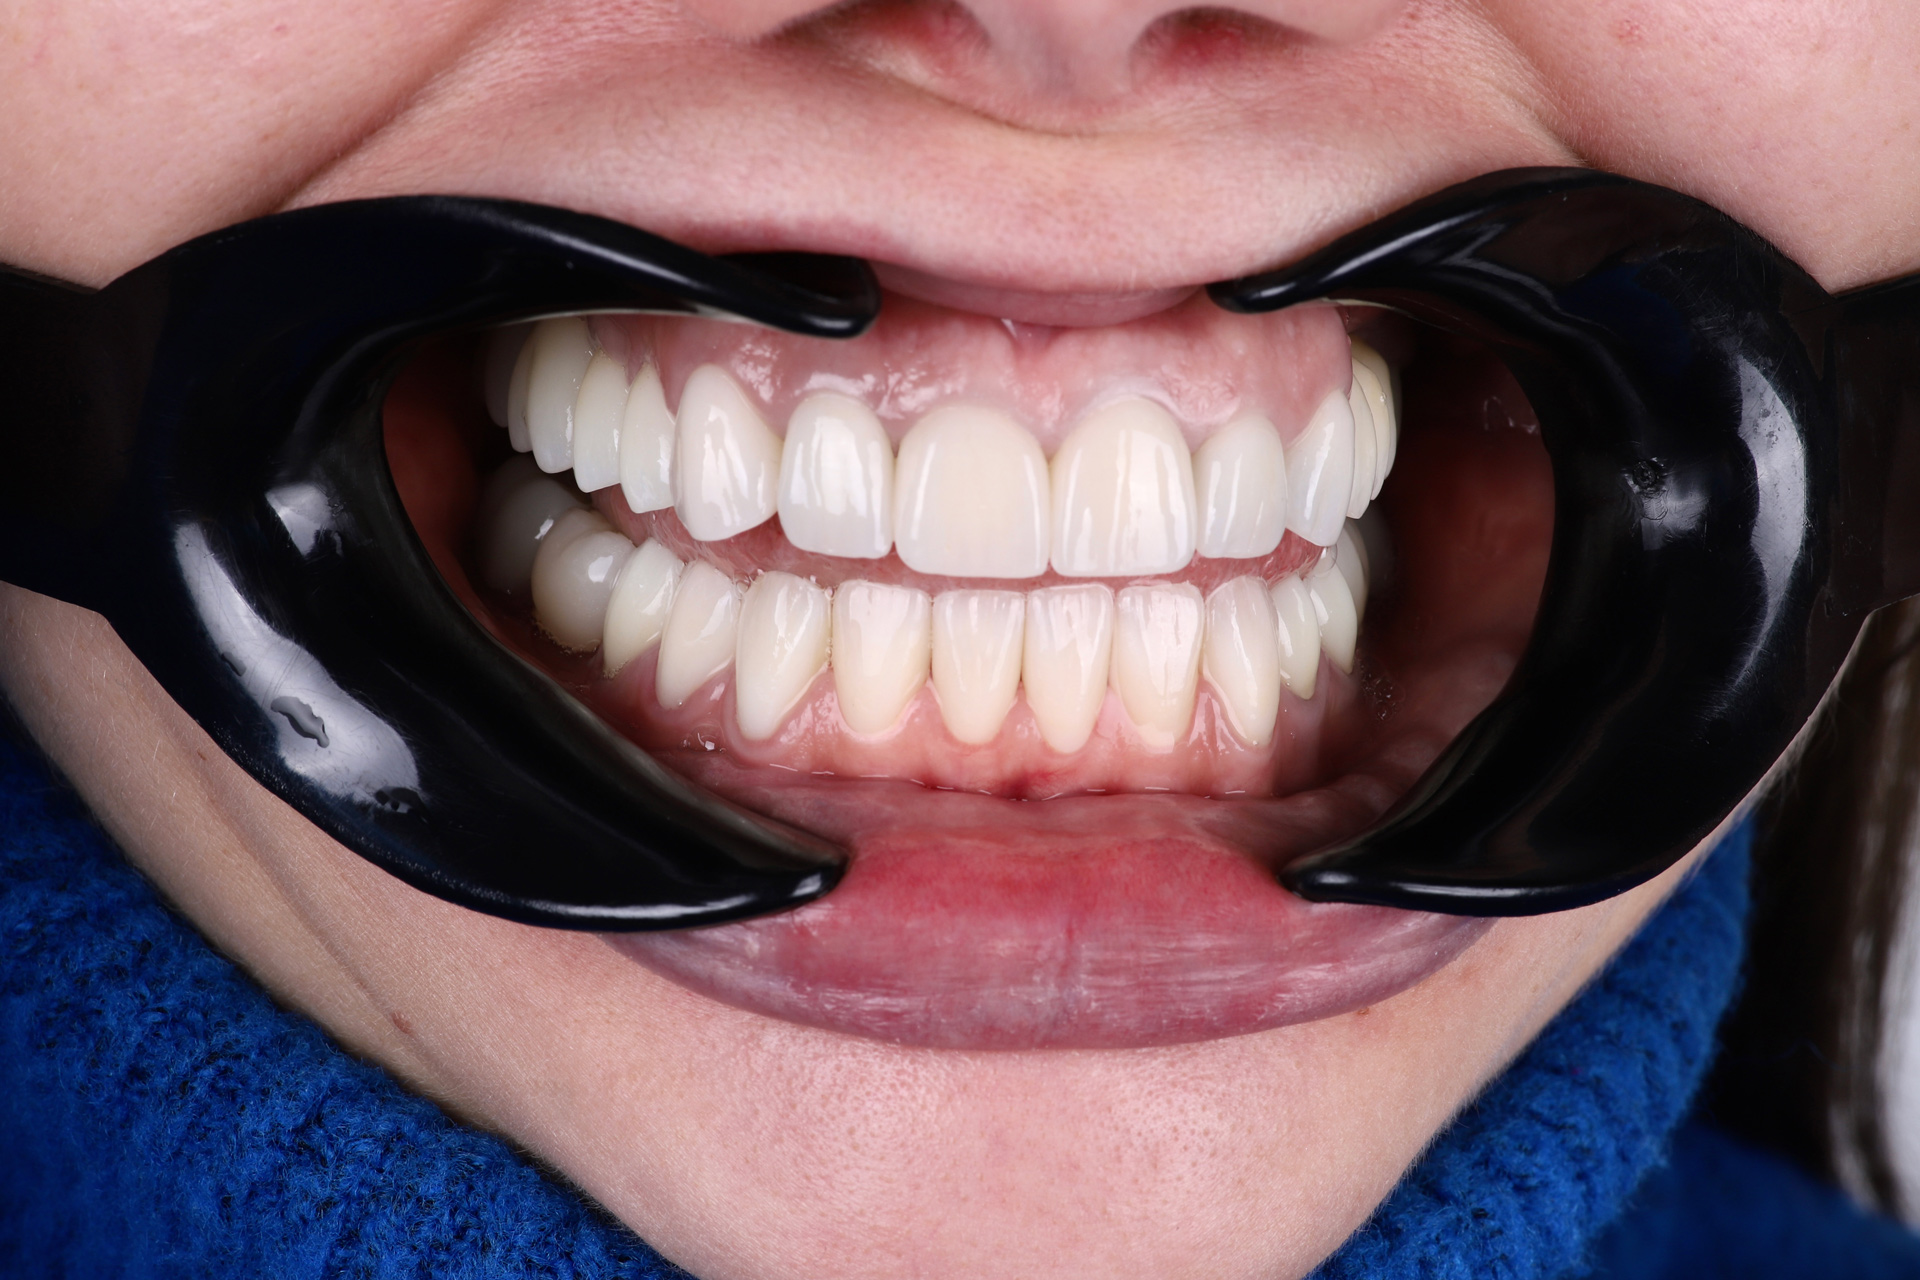

І настала війна… Після 1,5 року ми зустрілись знову. А частини тимчасових зубів вже не було, але положення щелеп та імплантанти збереглись. Тому дуже швидко перевели роботу з тимчасових коронок на постійні. Загалом було встановлено всі види ортопедичних конструкцій: коронки, вініри та керамічні накладки.

Олена не стримувала емоції, коли вперше побачила свою оновлену усмішку. І навіть сльози радості не зіпсували нову сяючу усмішку. Олена і досі отримує компліменти від знайомих та близьких стосовно її нового вигляду та яскравості усмішки.